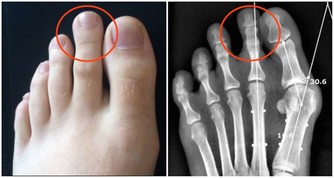

西醫認為,手腳麻木是痺栓引起的。“痺栓”,沉積在神經通路里,是神經細胞代謝物、神經毒素相互吸附粘合而成,就像電線中間有段橡皮膠,使生物電流無法通過,病人感覺手腳麻木。

事實的確如此。老人癱瘓之前就一直嘮叨:手腳發麻,胳膊抬不起,手握不住東西,連上廁所提褲子都費勁。哪裡知道,就在老人癱瘓前兩個月,體內痺栓急劇上升,老人身體不斷發出不祥信號:抽筋,手指就像木頭一樣,什麼感覺都沒有,並且疼痛加重。如果老人這個時候吃點清洗痺栓的藥,就不會癱在床上。遺憾的是,兒女們沒有把它當回事,才造成今天的結果。有些病人會出現“無痛”心髒病,其最關鍵的前兆是:突發暈眩、心跳加劇、氣短、噁心、嘔吐、冒冷汗。如果身體出現上述某些症狀,要第一時間打120急救。病人口中可含一片阿司匹林或硝酸甘油,以防心髒病發作時心肌受到損傷。